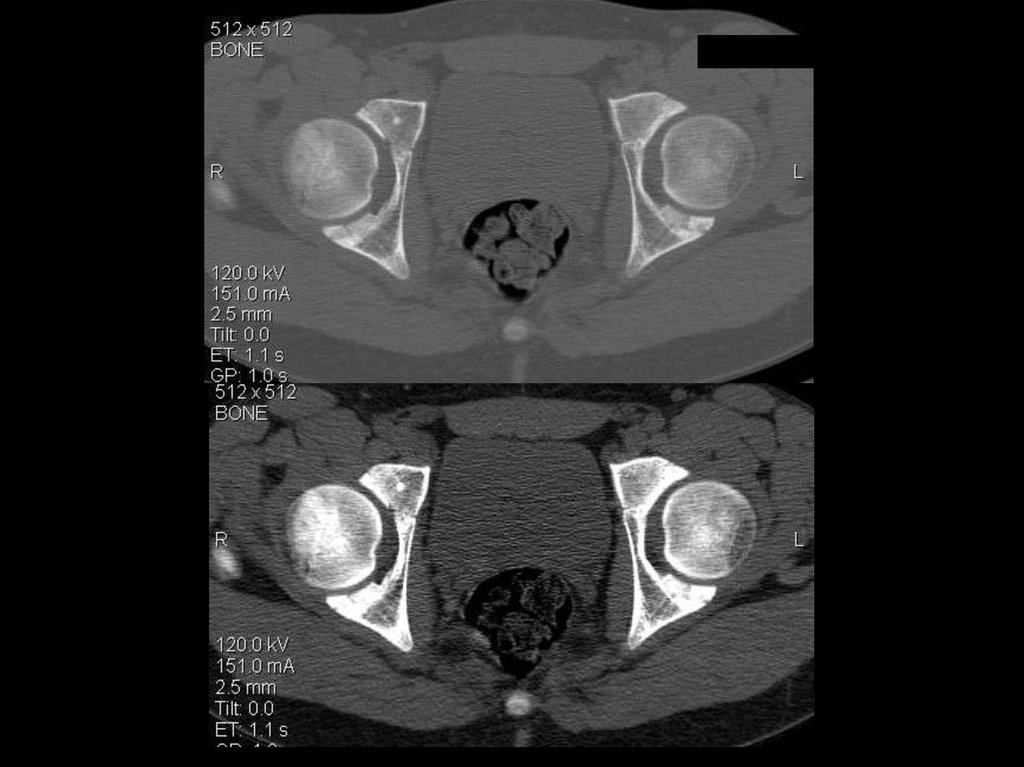

исследование тазобедренных суставов

Ток: 150 мА

Напряжение: 120кВ

Толщина среза: 2.5 мм

Матрица: 512х512

Режим: спиральный, 15 мм/с